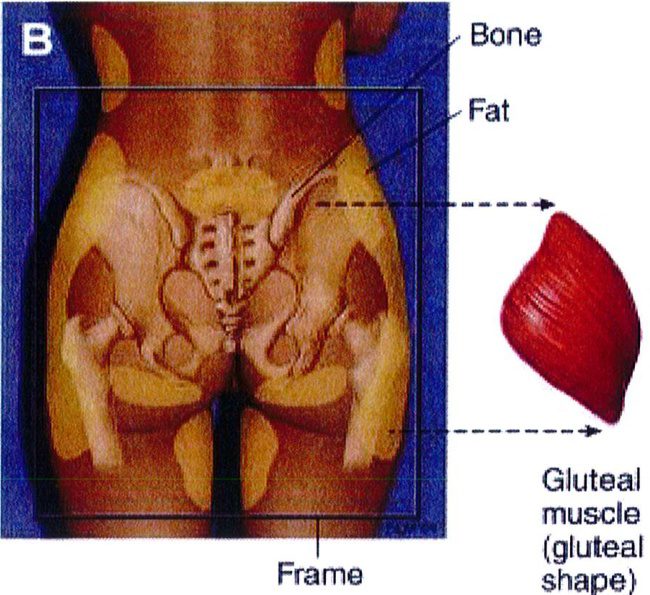

Các đơn vị thẩm mỹ vùng mông là khái niệm quy định các vùng thẩm mỹ khác nhau của mông. Hiểu được các đơn vị thẩm mỹ này và mối quan hệ của chúng với khu- ng chậu là điều tối quan trọng trước khi thực hiện nâng mông. Các đơn vị này được sử dụng để định hướng và xác định khu vực nào sẽ được nhận Mỡ, khu vực nào sẽ được hút mỡ, điều này sẽ ảnh hưởng tới kết quả, vì thế chúng ta cần thảo luận kỹ. Công trình đã xuất bản trước đây đã mô tả 10 đơn vị thẩm mỹ cho vùng sau (Hình 2), và một công trình khác đã mô tả 8 đơn vị thẩm mỹ vùng mông: 2 đơn vị mạn sườn, 1 đơn vị tam giác cùng, 1 đơn vị

Aesthetic Units/ Zones

Hình. 2. (A) 10 đơn vị thẩm mỹ vùng sau được mô tả. (B,C) Sau khu vực quan trọng xác định hình dạng khung; bao gồm vùng 1 – 5 và vùng 8. (C) Vùng 8 có thế yêu cầu ghép mô mỡ để tạo đường bờ đẹp (Từ bài báo của Mendieta CG. Gluteal reshaping. Aesthet Surg J 2007;27(6):641-55)

Aesthetic Unit/Zones:Đơn vị thẩm mỹ vùng mông.

1.Sacrum V-zone: Vùng cũng chữ V. 2.Flank: Hông.

7.Diamond zone:inner gluteal/leg injection: Vùng hình thoi: Vùng đùi trong/vùng hút mỡ. 8.Mid-lateral buttock point:Điểm C. 9.Inferior gluteal /posterior leg junc- tion: Mặt sau đùi/mặt dưới mông. 10.Upper back: Lưng.

Aesthetic Unit/Zones:Đơn vị thẩm mỹ vùng mông. 1.Sacrum V-zone: Vùng cũng chữ V. 2.Flank: Hông. 3. Upper buttock : Mông trên, 4. Lower back: Thắt lưng. 5.Outer leg : Bờ ngoài đùi. 6. Gluteus: Mông.

8.Mid-lateral buttock point:Điểm C. 9.Inferior gluteal /posterior leg junc- tion: Mặt sau đùi/mặt dưới mông. 10. Upper back: Lưng.

3.Upper buttock : Mông trên, 4. Lower back: Thắt lưng. 5.Outer leg : Bờ ngoài đùi. 6. Gluteus: Mông.

Hình. 3. 8 đơn vị thấm mỹ vùng mông bao gôm 2 mạn sườn đối xứng 2 bên (1,2), 1 tam giác cùng (3), mông hai bên (4,5), 2 đùi sau đối xứng nhau (7 và 8), và 1 bộ phận giao thoa của 2 nếp lắn mông (hình thoi – 6) (Nguồn: Centeno RF. Gluteal aesthetic unit classification: a tool to improve outcomes in body contouring. Aes- thetic Surg J 2006;26(2):200-8)